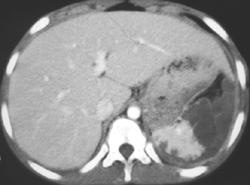

Gauchers Disease